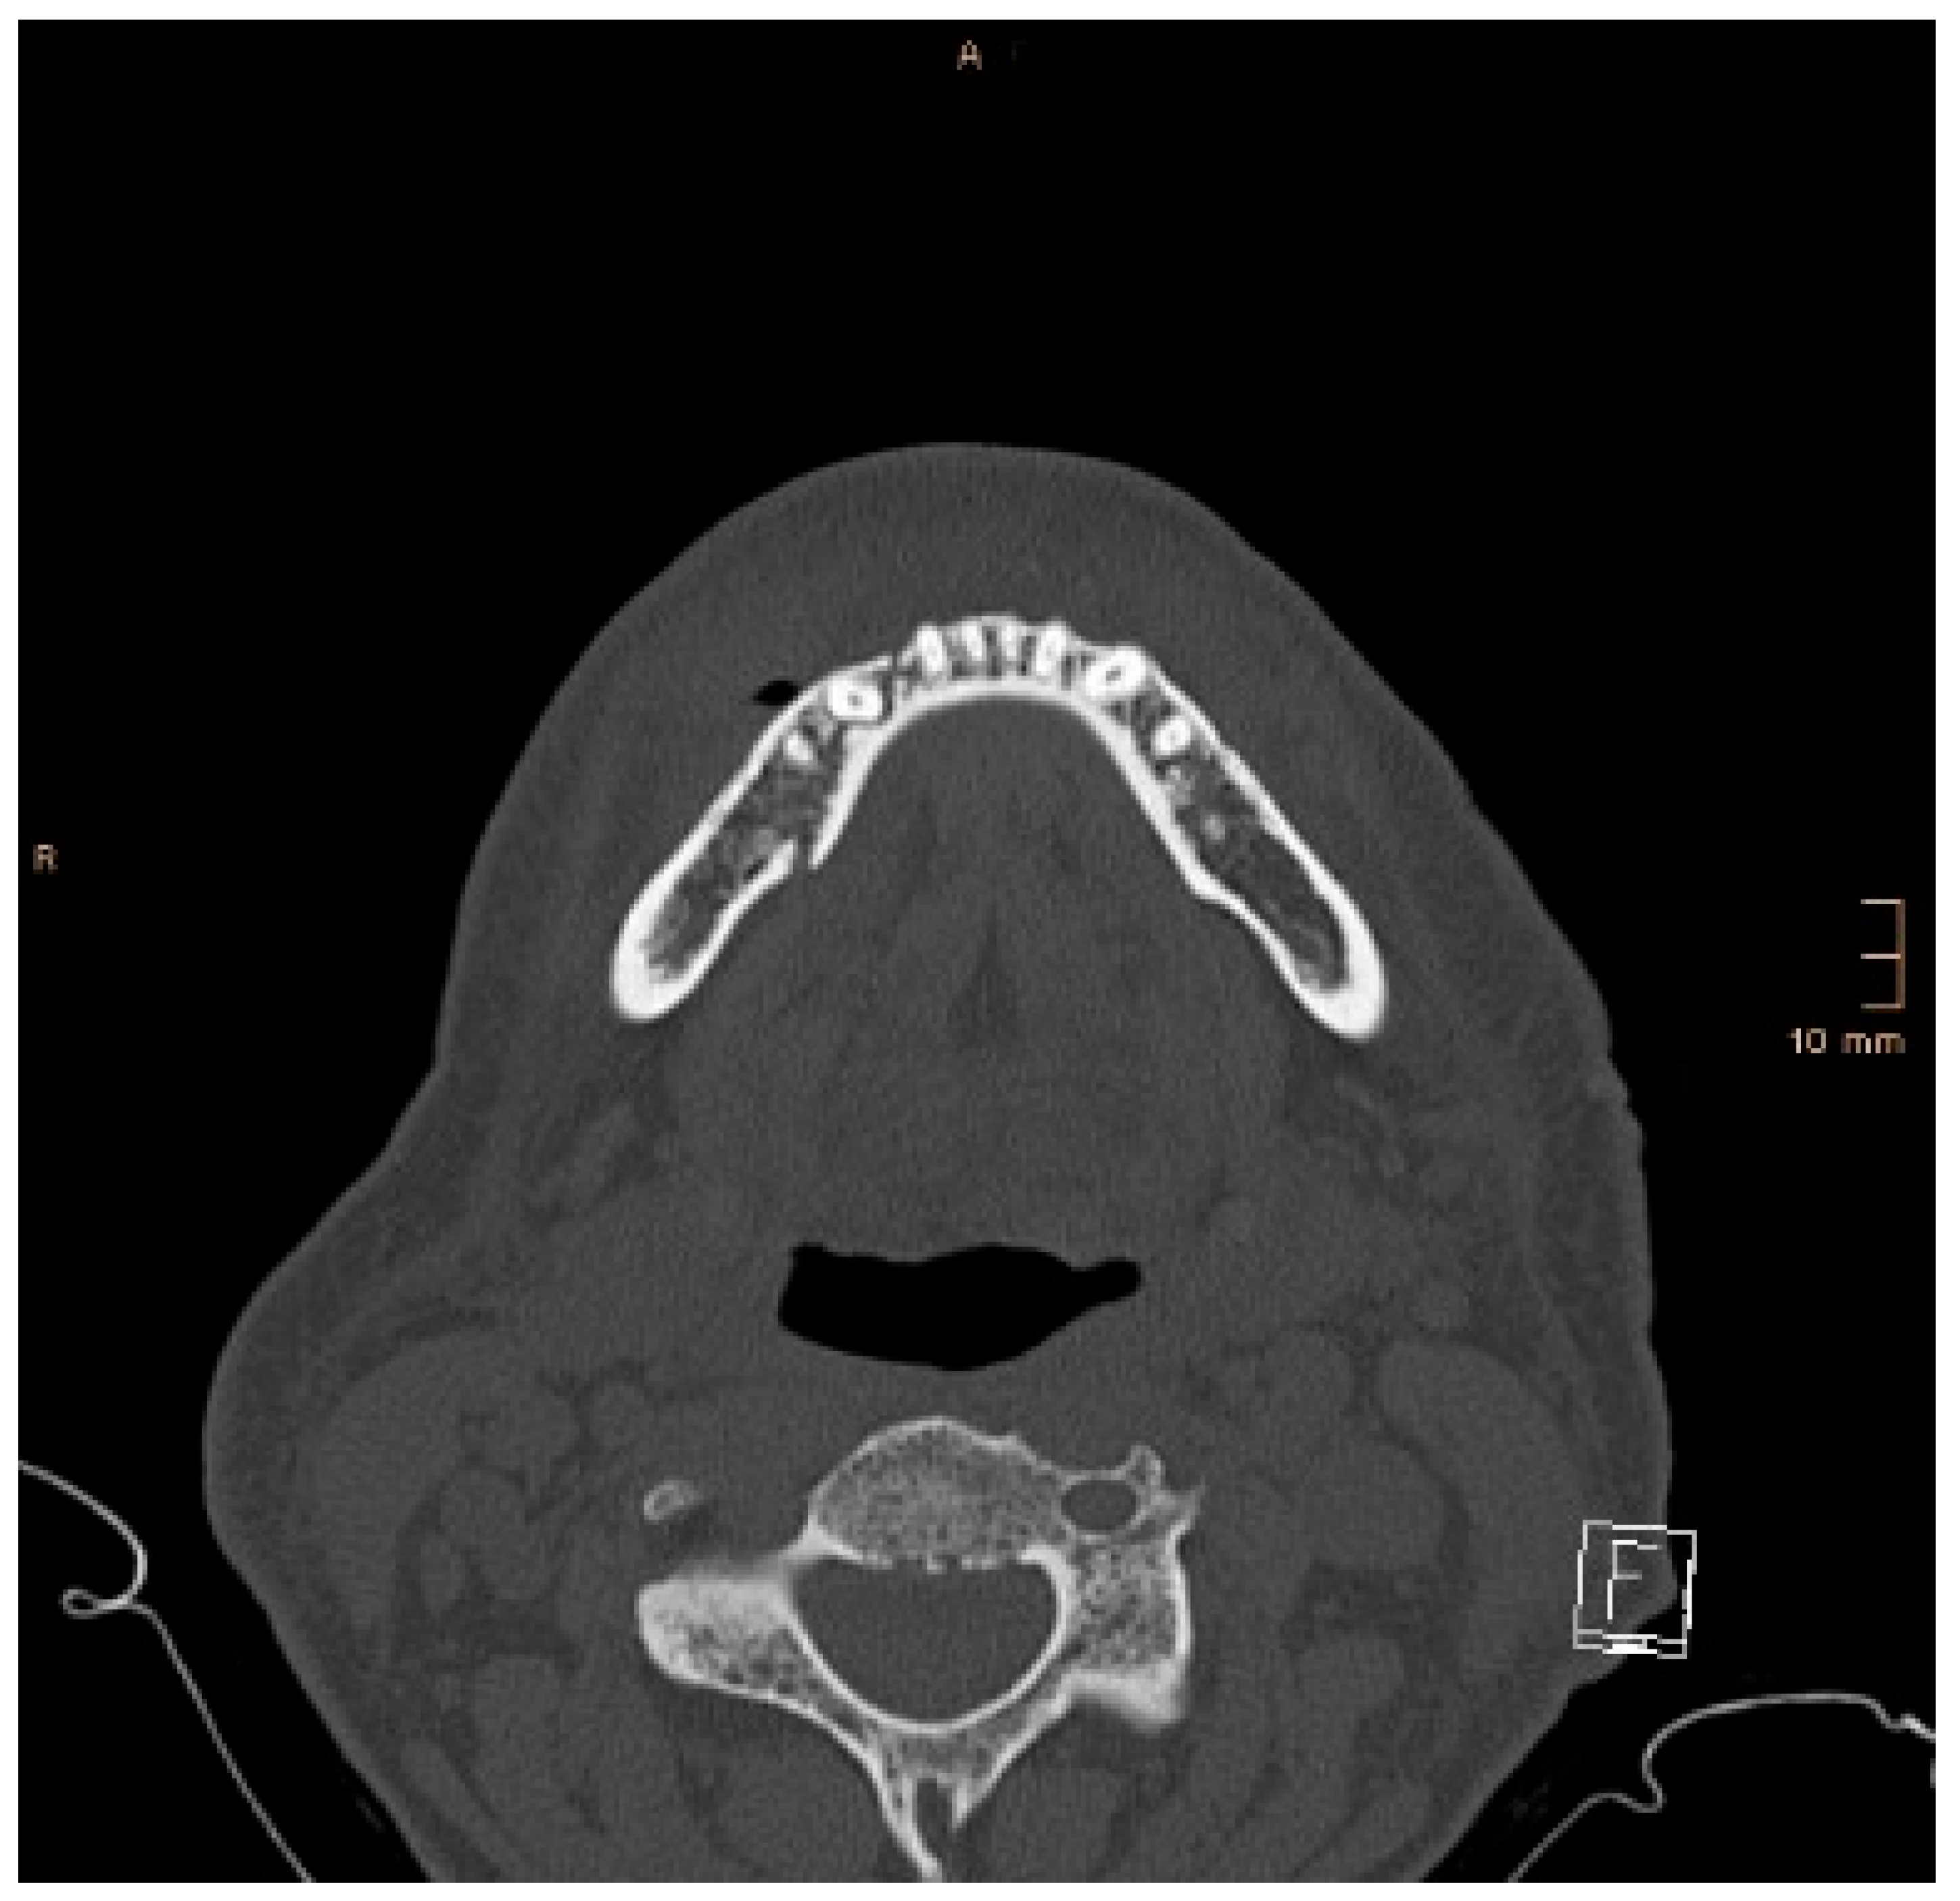

Two operations had to be redone because of inadequate reposition in the symphysis/parasymphysis with broad (>2 mm) lingual splay. In both cases, straight miniplates were removed. Osteosynthesis was achieved with lag screws. Figure 3 depicts plate osteosynthesis of a symphyseal fracture with a broad lingual gap (Figure 3). Figure 4 shows the same patient after redo operation and osteosynthesis of the same fracture with a lag-screw and a marked reduction in the lingual splaying (Figure 4). Figure 5 demonstrates the condylar reduction in the frontal plane in the same patient. Figure 6 and Figure 7 show the patient’s occlusion (Figure 5, Figure 6 and Figure 7). The third redo operation was due to nonunion and infection of an angular fracture with fracture of the two condylar plates. In this case, after removal of the infected miniplate, the angle fracture was stabilized with a reconstruction plate and a miniplate from an extraoral approach; the two broken miniplates at the condylar process were left in situ.

Figure 3. Axial CT scan with splaying of the lingual cortical bone in a symphyseal mandibular fracture after treatment with miniplates.

Figure 4. Axial CT scan showing the same patient as in Figure 3 after replacing the miniplates with a lag screw and considerable closure of the lingual gap. However, a small gap in the lingual cortical bone remained, and possibly determined a widening of the mandible.